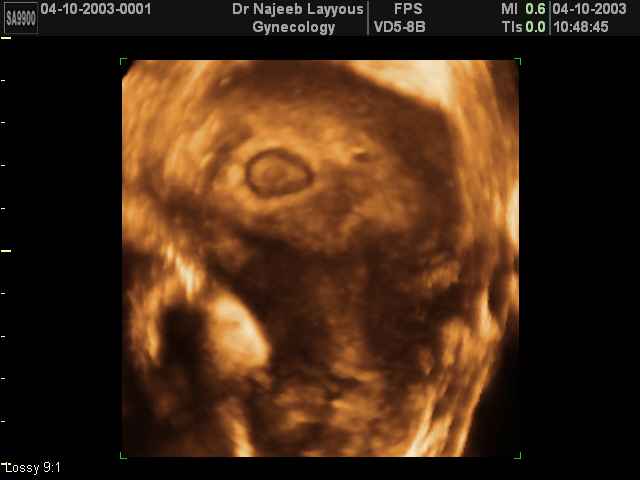

3D First Trimester Ultrasound Scan Photos ( Early Pregnancy Ultrasound Photos ) | Dr N Layyous

3D First Trimester Ultrasound Scan Photos